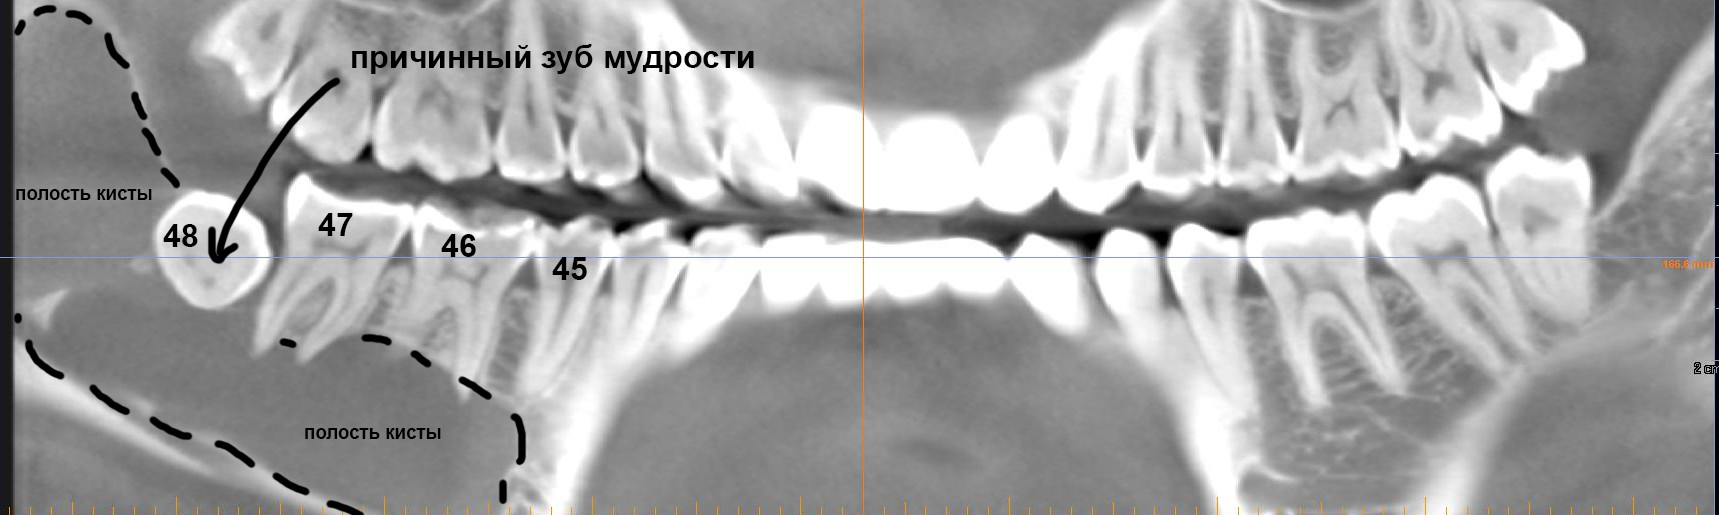

Во-первых, среди докторов нет чёткого представления о том, что считать периимплантитом. Можно ли назвать периимплантитом, например, вот такое?

Во-вторых, из-за неразберихи в терминологии и симптоматике, статистика перимплантитов — это, в общем-то, отсутствие статистики: одни Ыксперты утверждают, что признаки периимплантита развивается чуть ли не в 80% случаев имплантации, другие говорят о 10-20-50% и, как вы понимаете, такой разброс в цифрах — главный признак ненаучности методов подсчёта.

В-третьих, нет однозначного мнения о причинах развития периимплантита. Диапазон предположений слишком уж широк: от банальной перегрузки и плохой гигиены до специфической микрофлоры и генетической патологии. Также существуют определённые сложности с диагностикой: 99% периимплантитов протекают бессимптомно и выявляются случайно, во время рентгенологического обследования совсем, назначенного по совсем другому поводу.